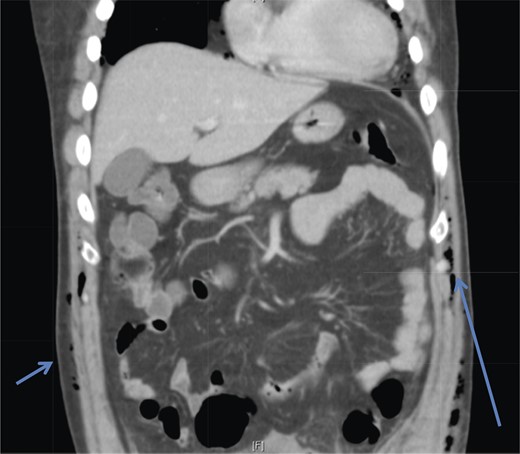

A 42-year-old male with a past medical history of hypertension was admitted for an elective TEP repair of his left inguinal hernia. Endotracheal intubation and general anesthesia were given uneventfully. The extraperitoneal space was developed with a balloon space maker, and insufflation of carbon dioxide at a maximum pressure of 12 mmHg was performed. Intraoperatively, a large incarcerated indirect left inguinal hernia containing omentum was reduced. A Optilene mesh (10 × 12 cm) was placed and tacked appropriately after hernia reduction. There were no obvious tears in the peritoneum and the total operative time was ∼90 min. No elevation of end-tidal CO2 was noted during the surgery and the patient was extubated successfully. The patient subsequently complained of left-sided chest pain on the same night of the surgery. He did not have abdominal pain. He had subcutaneous crepitus extending from the left groin to the left chest. His cardiac enzymes were negative and his electrocardiography revealed a sinus rhythm with no acute ischemic changes. A plain radiograph of the chest showed a sliver of lucency in the mediastinum suspicious for pneumomediastinum, with no obvious pneumoperitoneum or pneumothorax seen (Fig. 1). Computed tomographic (CT) imaging of the thorax and abdomen confirmed the radiograph finding of pneumomediastinum and diffuse subcutaneous emphysema tracking along the abdominal muscles bilaterally, as well as a small amount of free air and stranding in the left posterior pararenal space (Figs 2–4). The patient was treated conservatively with oral analgesia and supplemental oxygen. His chest pain resolved by the third postoperative day and he was discharged well. He was advised to avoid air travel for 1 month. He was reviewed in clinic at the 1-week and 1-month intervals and did not report any further chest pain or respiratory symptoms. His operation site healed well and he remained recurrence free.

Coronal section CT abdomen scan demonstrates tracking of subcutaneous emphysema (arrowheads).